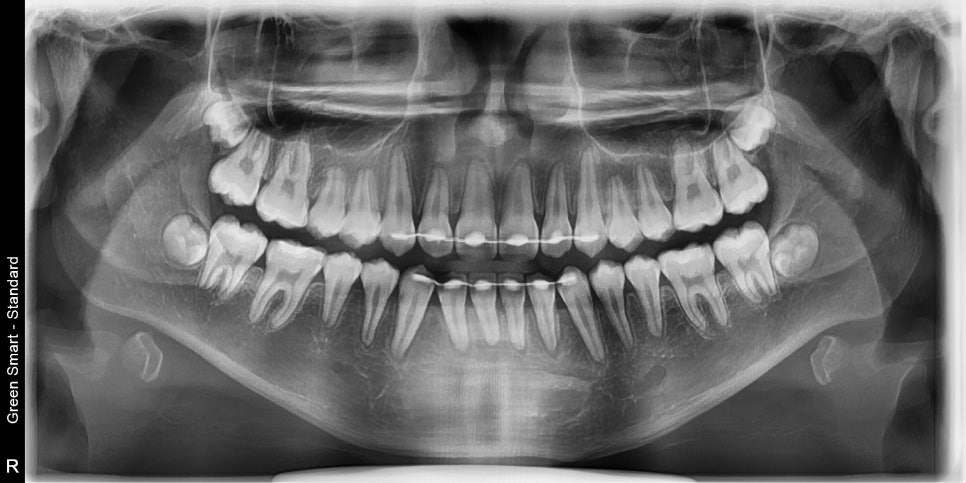

교정 치료 중에 화살표 최후방 치아가 맹출하여,

이 치아를 배열하는 과정에서 치료가 조금 더 길어지긴 했습니다

최후방 치아가 나올때 약간 삐뚤게 나옴으로 인해 1회 재제작을 했습니다.

이 덧니 교정 사례에서는 2023년 6월 초부터 2024년 11월 11일까지 약 1년 5개월간 치료를 진행했습니다. 치료 중 최후방 치아 맹출로 인해 1회 재제작을 하여 치료기간이 조금 더 길어졌습니다.